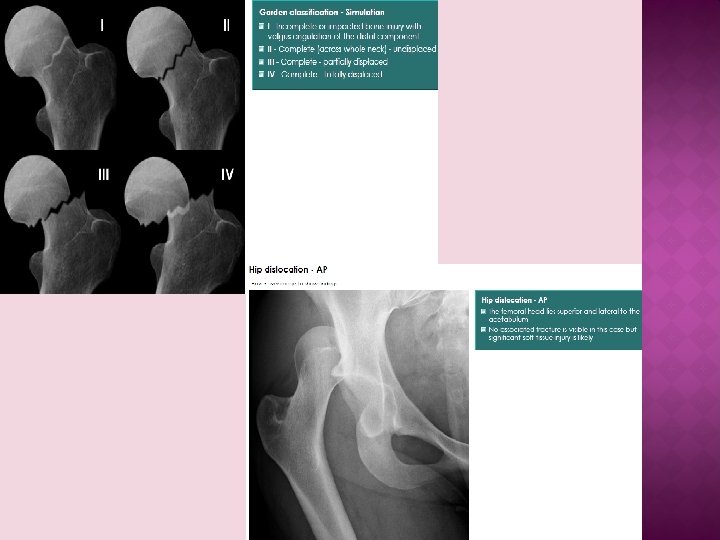

RADIOLOGICAL FX Osteoporotic bones